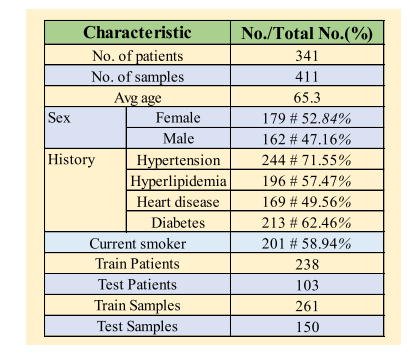

Fig. 3. Comprehensive demographic and angiographic information of AmTICIS.

图3:自动改良脑梗死溶栓分级评分(AmTICIS)数据集的综合人口统计学和血管造影信息。